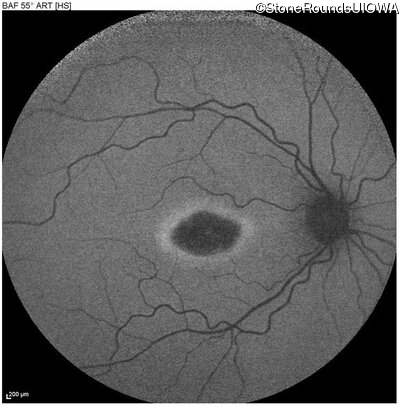

This 22 year old man had macular abnormalities noted incidentally at a routine eye exam at age 19. Since then, he has experienced a gradual loss of acuity particularly in the left eye.

| AR Stargardt Disease | ABCA4 | Tyr245Stop TAT>TAG | Unknown | AR |